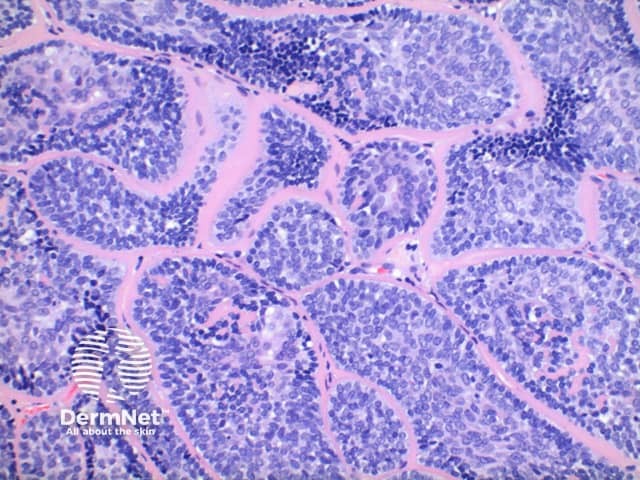

Low power view of cylindroma shows a non-encapsulated tumour nodule arising from the dermis (Figure 1). This is formed by multiple irregular tumour islands, distributed in an aptly named ‘jigsaw’ pattern (Figure 2). Surrounding the tumour islands, and in discrete droplets within the nodules is a thick hyaline deposit (Figure 3). Two populations of cells are noted to make up the tumour nodules. A smaller cell with a hyperchromatic nucleus tending to the periphery, and larger cells with open nuclei throughout the centre of the nodules (Figure 4).

Figure 3

The hyaline bands and deposits are PAS positive and diastase resistant, and are known to contain type IV and type VII collagen.